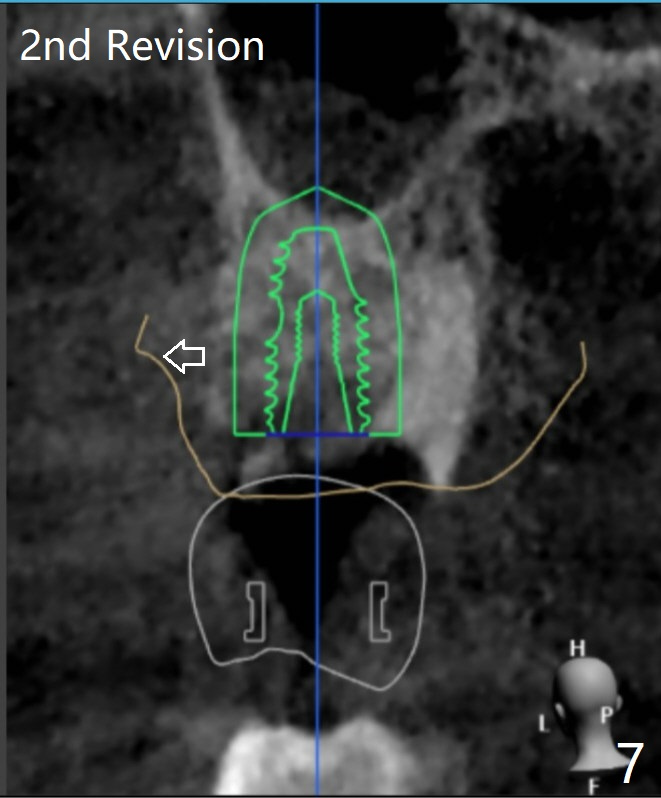

The FC implant will be placed more buccal (compare Fig.5-7).  Sinus lift is required most likely.